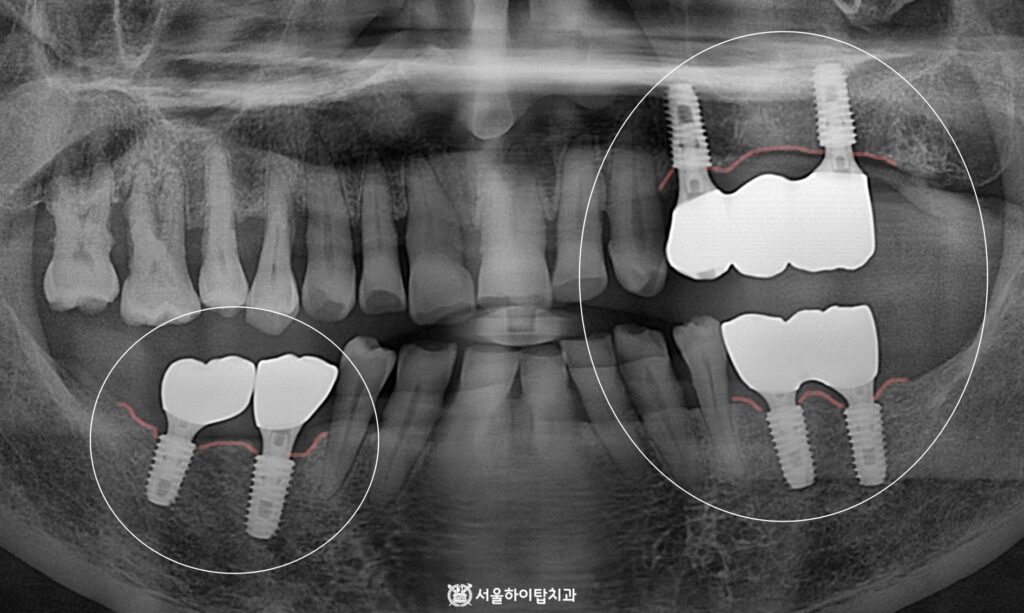

4. 최종 결과

골 융합이 충분히 이루어졌으며,

지르코니아 크라운으로 제작되면서

기능과 심미 모두 만족스러운 결과를

얻은 것으로 보여집니다.

이제는 양쪽 구치부를 활용한

균등한 저작을 할 수 있으며,